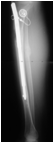

20/07 Post Op

• 19 mm distraction

• No pain

• Regained preoperative ROM

in knee and ankle

30/07 Post Distraction

Lengthening of 29mm – pelvis equal

Patient feels comfortable

Full ROM (same as pre-operatively)

Note proximal migration of distal fibula

Ceased lengthening.

Now Consolidation Phase with PWB

4 months Post Op

•No pain, asymptomatic

•Consolidation of 3 cortices- anterior no callus formation

•FWB now

•No restrictions

6 months Post Op

Callus formation anteriorly

24 months Post Op